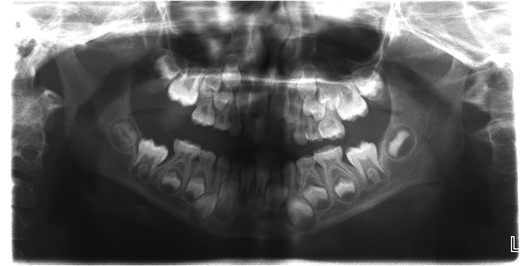

Computerized tomography (CT) image of the normal right temporomandibular joint.